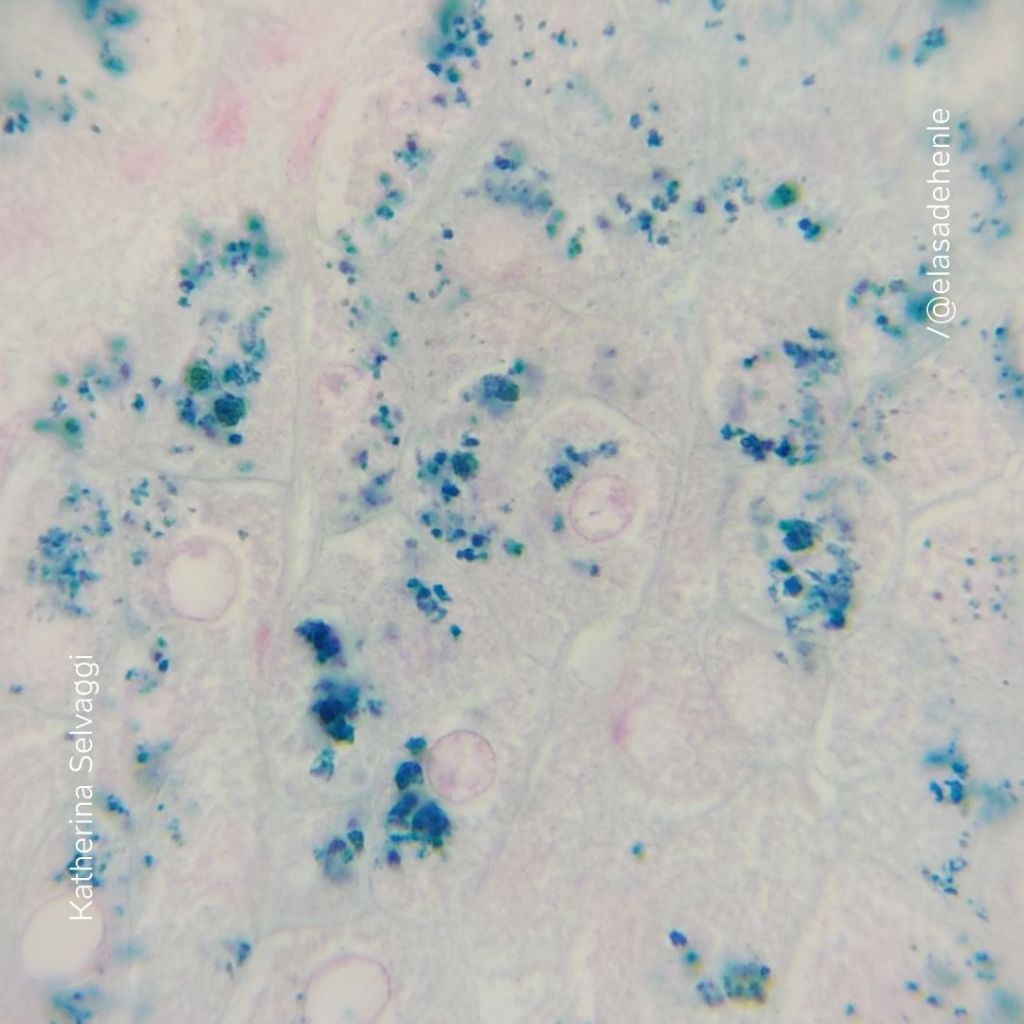

Perls

Hígado

EUTM